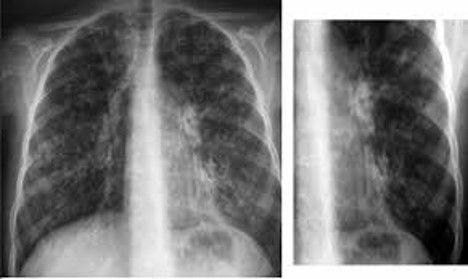

Las complicaciones respiratorias con una causa importante de morbilidad y mortalidad en personas con tetraplejia aguda y crónica. La debilidad

La disfunción muscular respiratoria en un importante problema de salud con alta prevalencia de morbi-mortalidad y coste económico asociado en